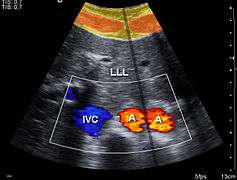

Clinical significance

In medicine, particularly optometry, ophthalmology and orthoptics, refraction (also known as refractometry) is a clinical test in which a phoropter may be used by the appropriate eye care professional to determine the eye's refractive error and the best corrective lenses to be prescribed. A series of test lenses in graded optical powers or focal lengths are presented to determine which provides the sharpest, clearest vision.[4]